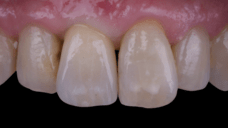

After an appropriate healing period, the definitive prosthesis was planned and delivered. A screw-retained zirconia crown was fabricated to ensure long-term durability, optimal esthetics, and retrievability. Zirconia was selected for its mechanical strength and excellent esthetic properties, blending seamlessly with the adjacent natural dentition in both form and color.

The final crown was designed to maintain the gingival architecture that had been shaped by the provisional. Special attention was paid to the emergence profile, contact points, and translucency to achieve harmony with the patient’s smile. The definitive restoration provided functional stability and esthetic integration, fulfilling the patient’s expectations for a fixed and natural solution.